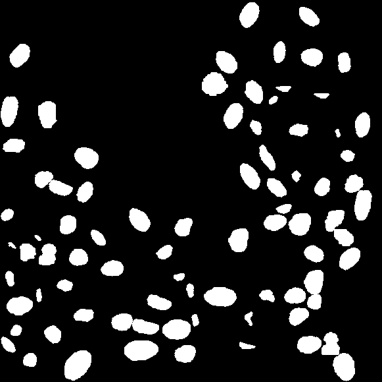

In our pipeline (Algorithm 1, Line 9), we employ AdaIN by using as content the (flattened) generated mask and as reference style a patch from a real image . We train for 30000 epochs using as DA flips and affine transformations for both style and content, and photometric transformations for the style image only. The output of AdaIN is a realistic image where the displayed cells follow the input . Pairs of generated image and mask can be used as annotated samples to augment the small annotated training set . Fig. 4 shows an example of this phase starting from a generated mask and using as reference style an image .

4 Experiments

We validate the effectiveness of our pipeline by training HoVerNet [11], a state-of-the-art instance segmentation NN, on our generated dataset. We start by generating training sets from small subsets of fluorescence microscopy images from the Broad Institute Repository (BBBC) [12]. We then assess the instance segmentation performance on real images from the NucleusSegData dataset [13]. As a baseline, we compare the performance of the same network trained on the full BBBC dataset (Full dataset) and on the few annotated images used for generation (Training real dataset) leveraging standard augmentations. We adopt as metrics those used in HoVerNet, i.e., DICE, DICE2, AJI and AJI+.

During the Blob Placement phase, we model as realizations of Perlin noise [14] as its complex 2D structures resemble a coarse view of the distribution of nuclei in histological images. We estimate the parameters of Perlin noise to maximize the similarity with blurred masks from training data. Then, we perform a preliminary analysis on the distributions of generated GTs to assess how close they are to real ones. In particular, we consider the distributions of area () and aspect ratio (), reporting close results in both the median (: 155px vs. 153px, : vs. ) and in the Inter-Quartile Range (: 32px vs. 39px, : vs. ).

For the image generation phase, we train AdaIN using a tiled version of real images. Then, for each generated mask , we select as reference image the tile having the closest number of blobs to . This choice improves the style transfer procedure, since AdaIN generates images having average value similar to the reference. When the style has too many blobs, artefacts may appear in the image, and when it has too few, the nuclei may be fainter than in real images.

Results shown in Table 1 and in Figure 5 indicate that HoVerNet trained on the full dataset ( annotated images, blobs) achieves an impressive DICE score and AJI score. These values need to be considered as an ideal standard and are displayed with a dashed line in Figure 5. When trained from a generated dataset starting from only two real images ( blobs), HoVerNet achieves DICE score and AJI score, compared to and when the same architecture is trained only on the same two real images. When increasing the number of real images this gap decreases, and the advantages of image generation are lost starting from real images ( blobs). Nonetheless, these results show that our pipeline enables to train models effectively even in very low data regimes.